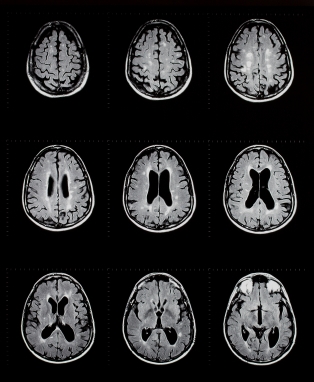

МРТ головного мозга без красителей

МРТ является магнитно-резонансная томография, специальный тест визуализации, которая не использует рентгеновских лучей. Эта процедура дает очень подробные изображения мозга, структуры лица, и пазух. В целом, МРТ лучше на выявление острых инсультов, инфекций и раковых заболеваний, чем компьютерная томография.